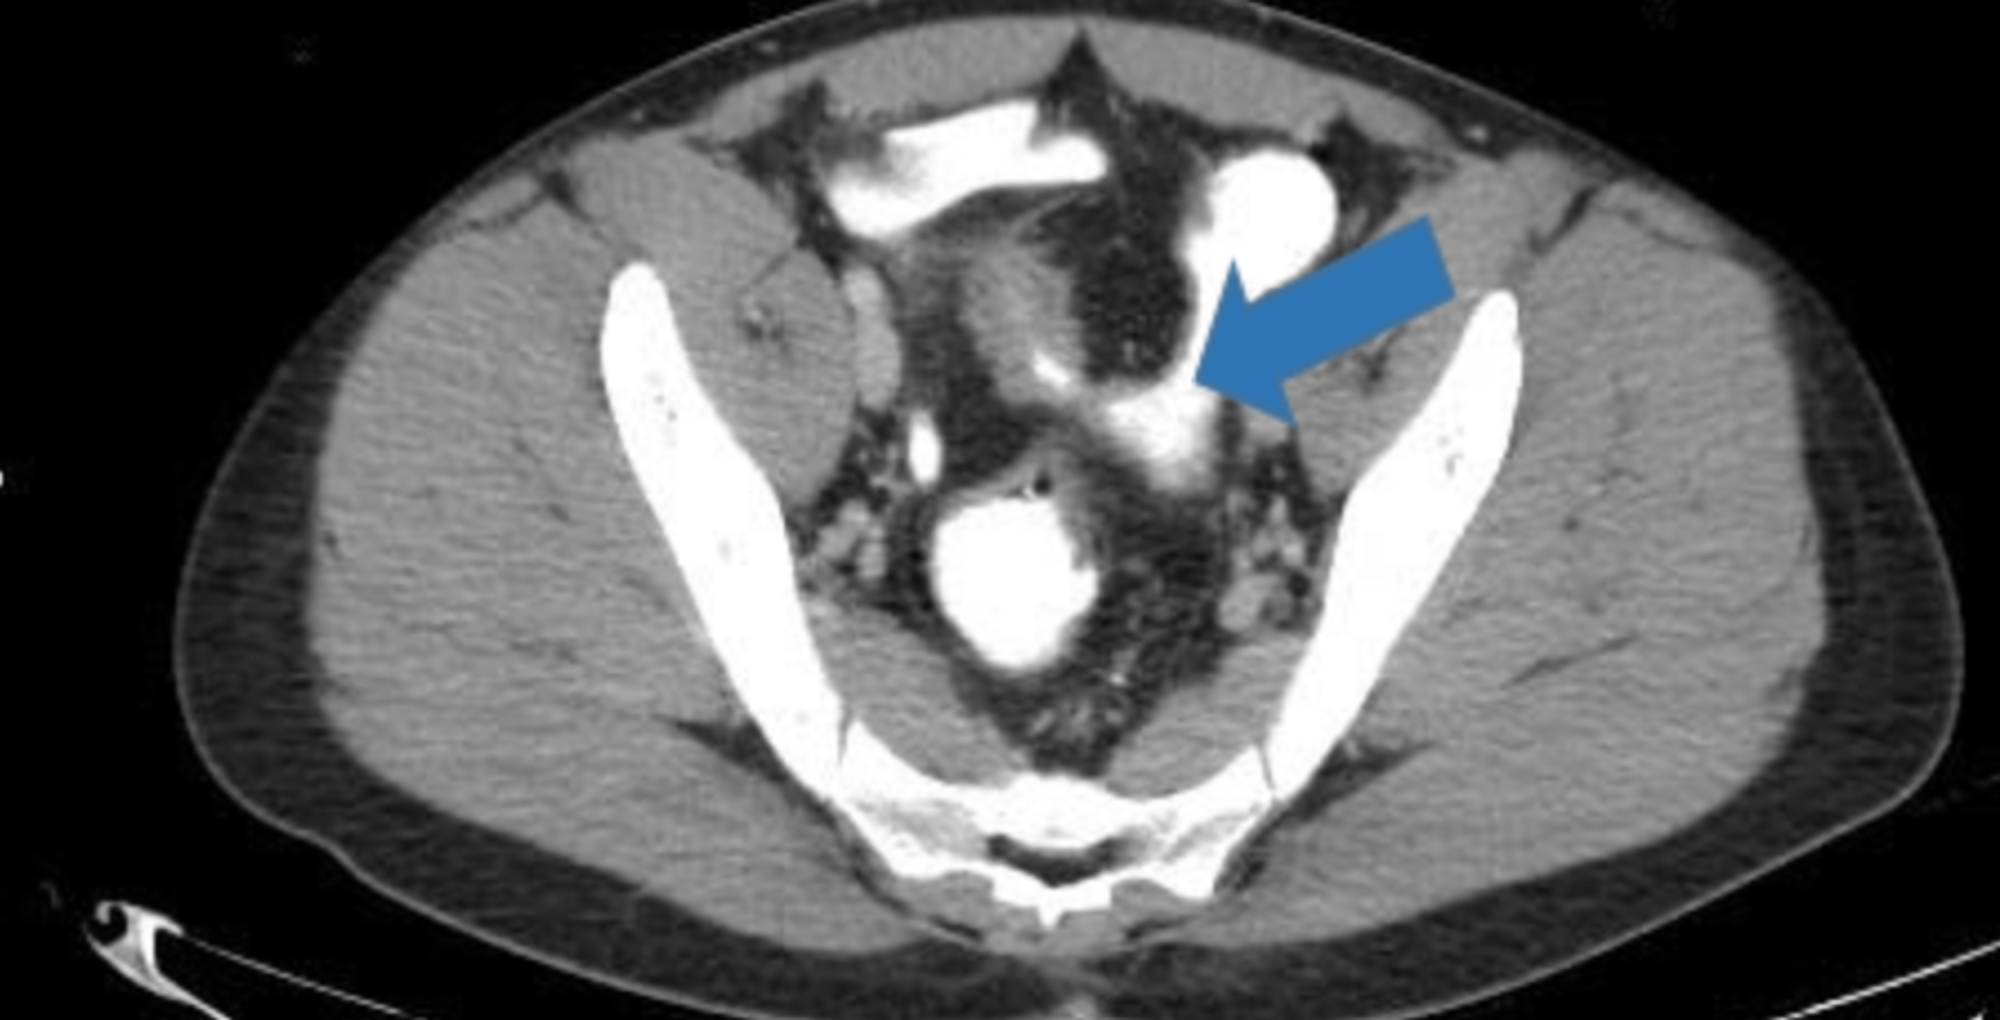

Urinary complications in Crohn’s disease and ulcerative colitis

(PDF) Crohn’s Disease and Urinary Manifestations A Crohn’s Intestinal Crohn's Disease Urine People diagnosed with crohn’s disease have a higher risk of developing kidney stones in the urinary tract than those without crohn’s, including those with ulcerative colitis. In people with crohn’s disease, hydronephrosis often occurs in the right kidney, close to the terminal ileum. Cystitis was the most common. Increased urination is one possible symptom of. Inflammatory bowel disease (ibd) is. Crohn's Disease Urine.

Cureus Recurrent Urinary Tract Infection in a Patient With Crohn's Disease Urine People diagnosed with crohn’s disease have a higher risk of developing kidney stones in the urinary tract than those without crohn’s, including those with ulcerative colitis. Ulcerative colitis (uc) and crohn disease (cd). Increased urination is one possible symptom of. Fistulizing crohn’s disease is caused by inflammation that results in the formation of a fistula —an abnormal channel between the.. Crohn's Disease Urine.

Cureus Recurrent Urinary Tract Infection in a Patient With Crohn's Disease Urine People with ulcerative colitis are more likely to develop kidney stones — hard deposits of salts and minerals in the kidneys. Increased urination is one possible symptom of. In people with crohn’s disease, hydronephrosis often occurs in the right kidney, close to the terminal ileum. Cystitis was the most common. People diagnosed with crohn’s disease have a higher risk of. Crohn's Disease Urine.

Crohn's disease. Contrastenhanced CT scan shows distal ileal loops Crohn's Disease Urine Ulcerative colitis (uc) and crohn disease (cd). People with ulcerative colitis are more likely to develop kidney stones — hard deposits of salts and minerals in the kidneys. Increased urination is one possible symptom of. Inflammatory bowel disease (ibd) is comprised of two major disorders: Cystitis was the most common. Crohn’s disease is a lifelong condition that causes inflammation in. Crohn's Disease Urine.